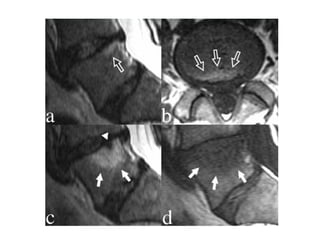

Modic type 1 deg. changes (MI)

Hypointense on T1WI (A)

Hyperintense on T2WI (B)

Modic changes

type 1 in

lower endplate

of L4

and

upper endplate

of L5

Modic Type I (Edema)

Modic type 2 degenerative

changes (MII)

hyperintense on T1WI (A)

isointense or slightly hyperintense on T2WI (B)

type 2 in the

the upper

endplate of S1